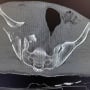

Solo dopo il trattamento dell'embolia, i medici hanno potuto passare alla ricostruzione del bacino, con quattro placche e ventiquattro viti. Dopo cinque settimane in Belgio sono poi seguite otto settimane di riabilitazione a Berlino. In tutto, Hollmann ha passato tre mesi interi su una sedia a rotelle.